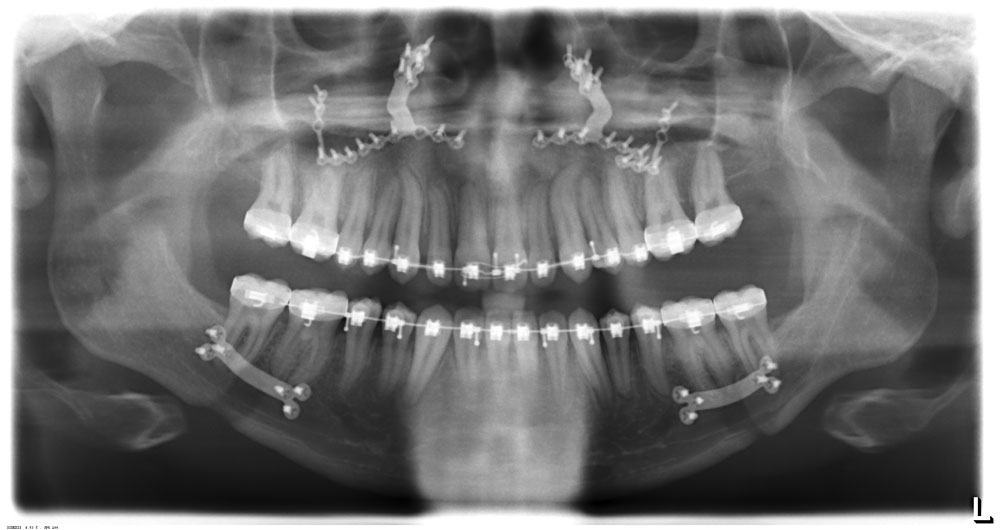

Getting everything straight. My double jaw surgery Xrays

Xray showing metal plates in the upper and lower jaws after surgery. Jaw surgery Double Jaw Surgery Xray Regain your confidence with this transformative procedure. Corrective jaw surgery, or orthognathic surgery, is a surgical procedure that involves moving one (single jaw surgery) or both jaws (double jaw surgery) into a new position, to create better alignment. They do a decent job of showing the drastic change that took place on the. A misaligned jaw can be due to. Double Jaw Surgery Xray.